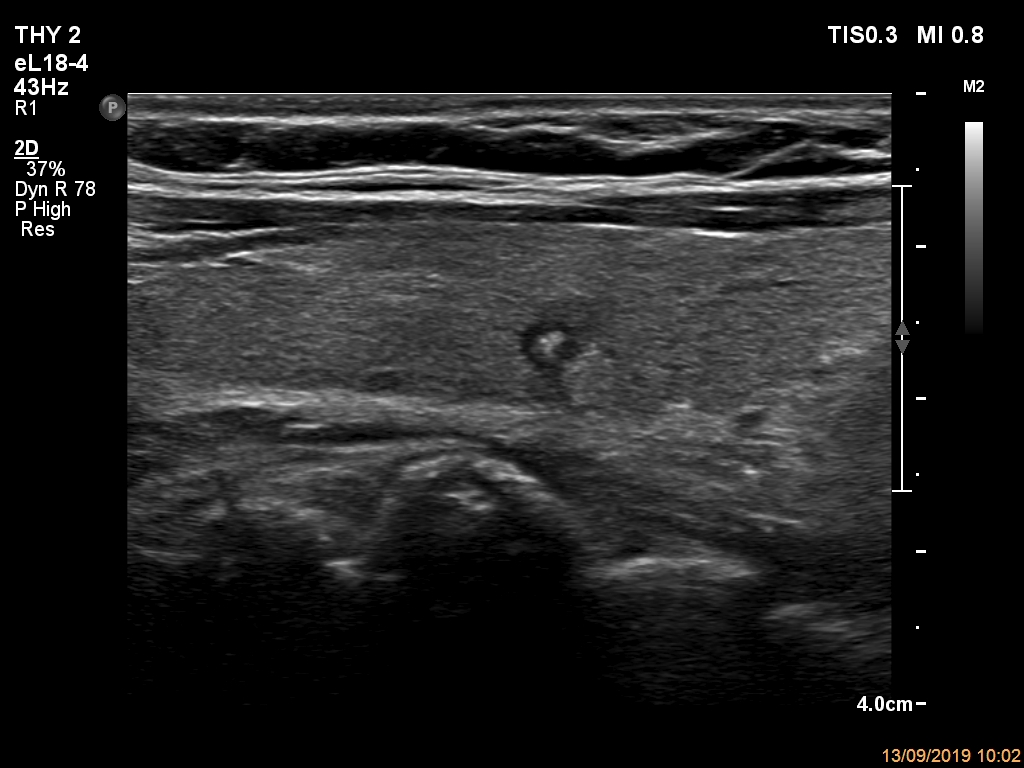

Ultrasonography. The thyroid was echonormal. There was a small hypoechogenic lesion in the central part of the right lobe. The lesion had microcalcification and non-parallel orientation, presented both taller-than-wide and taller-than-long shape. The left lobe had a hypoechogenic mass composed of discrete lesions. The whole mass displayed undulated margins which corresponded to non-pathological lobulation. On the other hand, a lesion within the mass had pathological, spiculated margins.

Comment. This case illustrates the difference between pathological and non-pathological forms of lobulation.